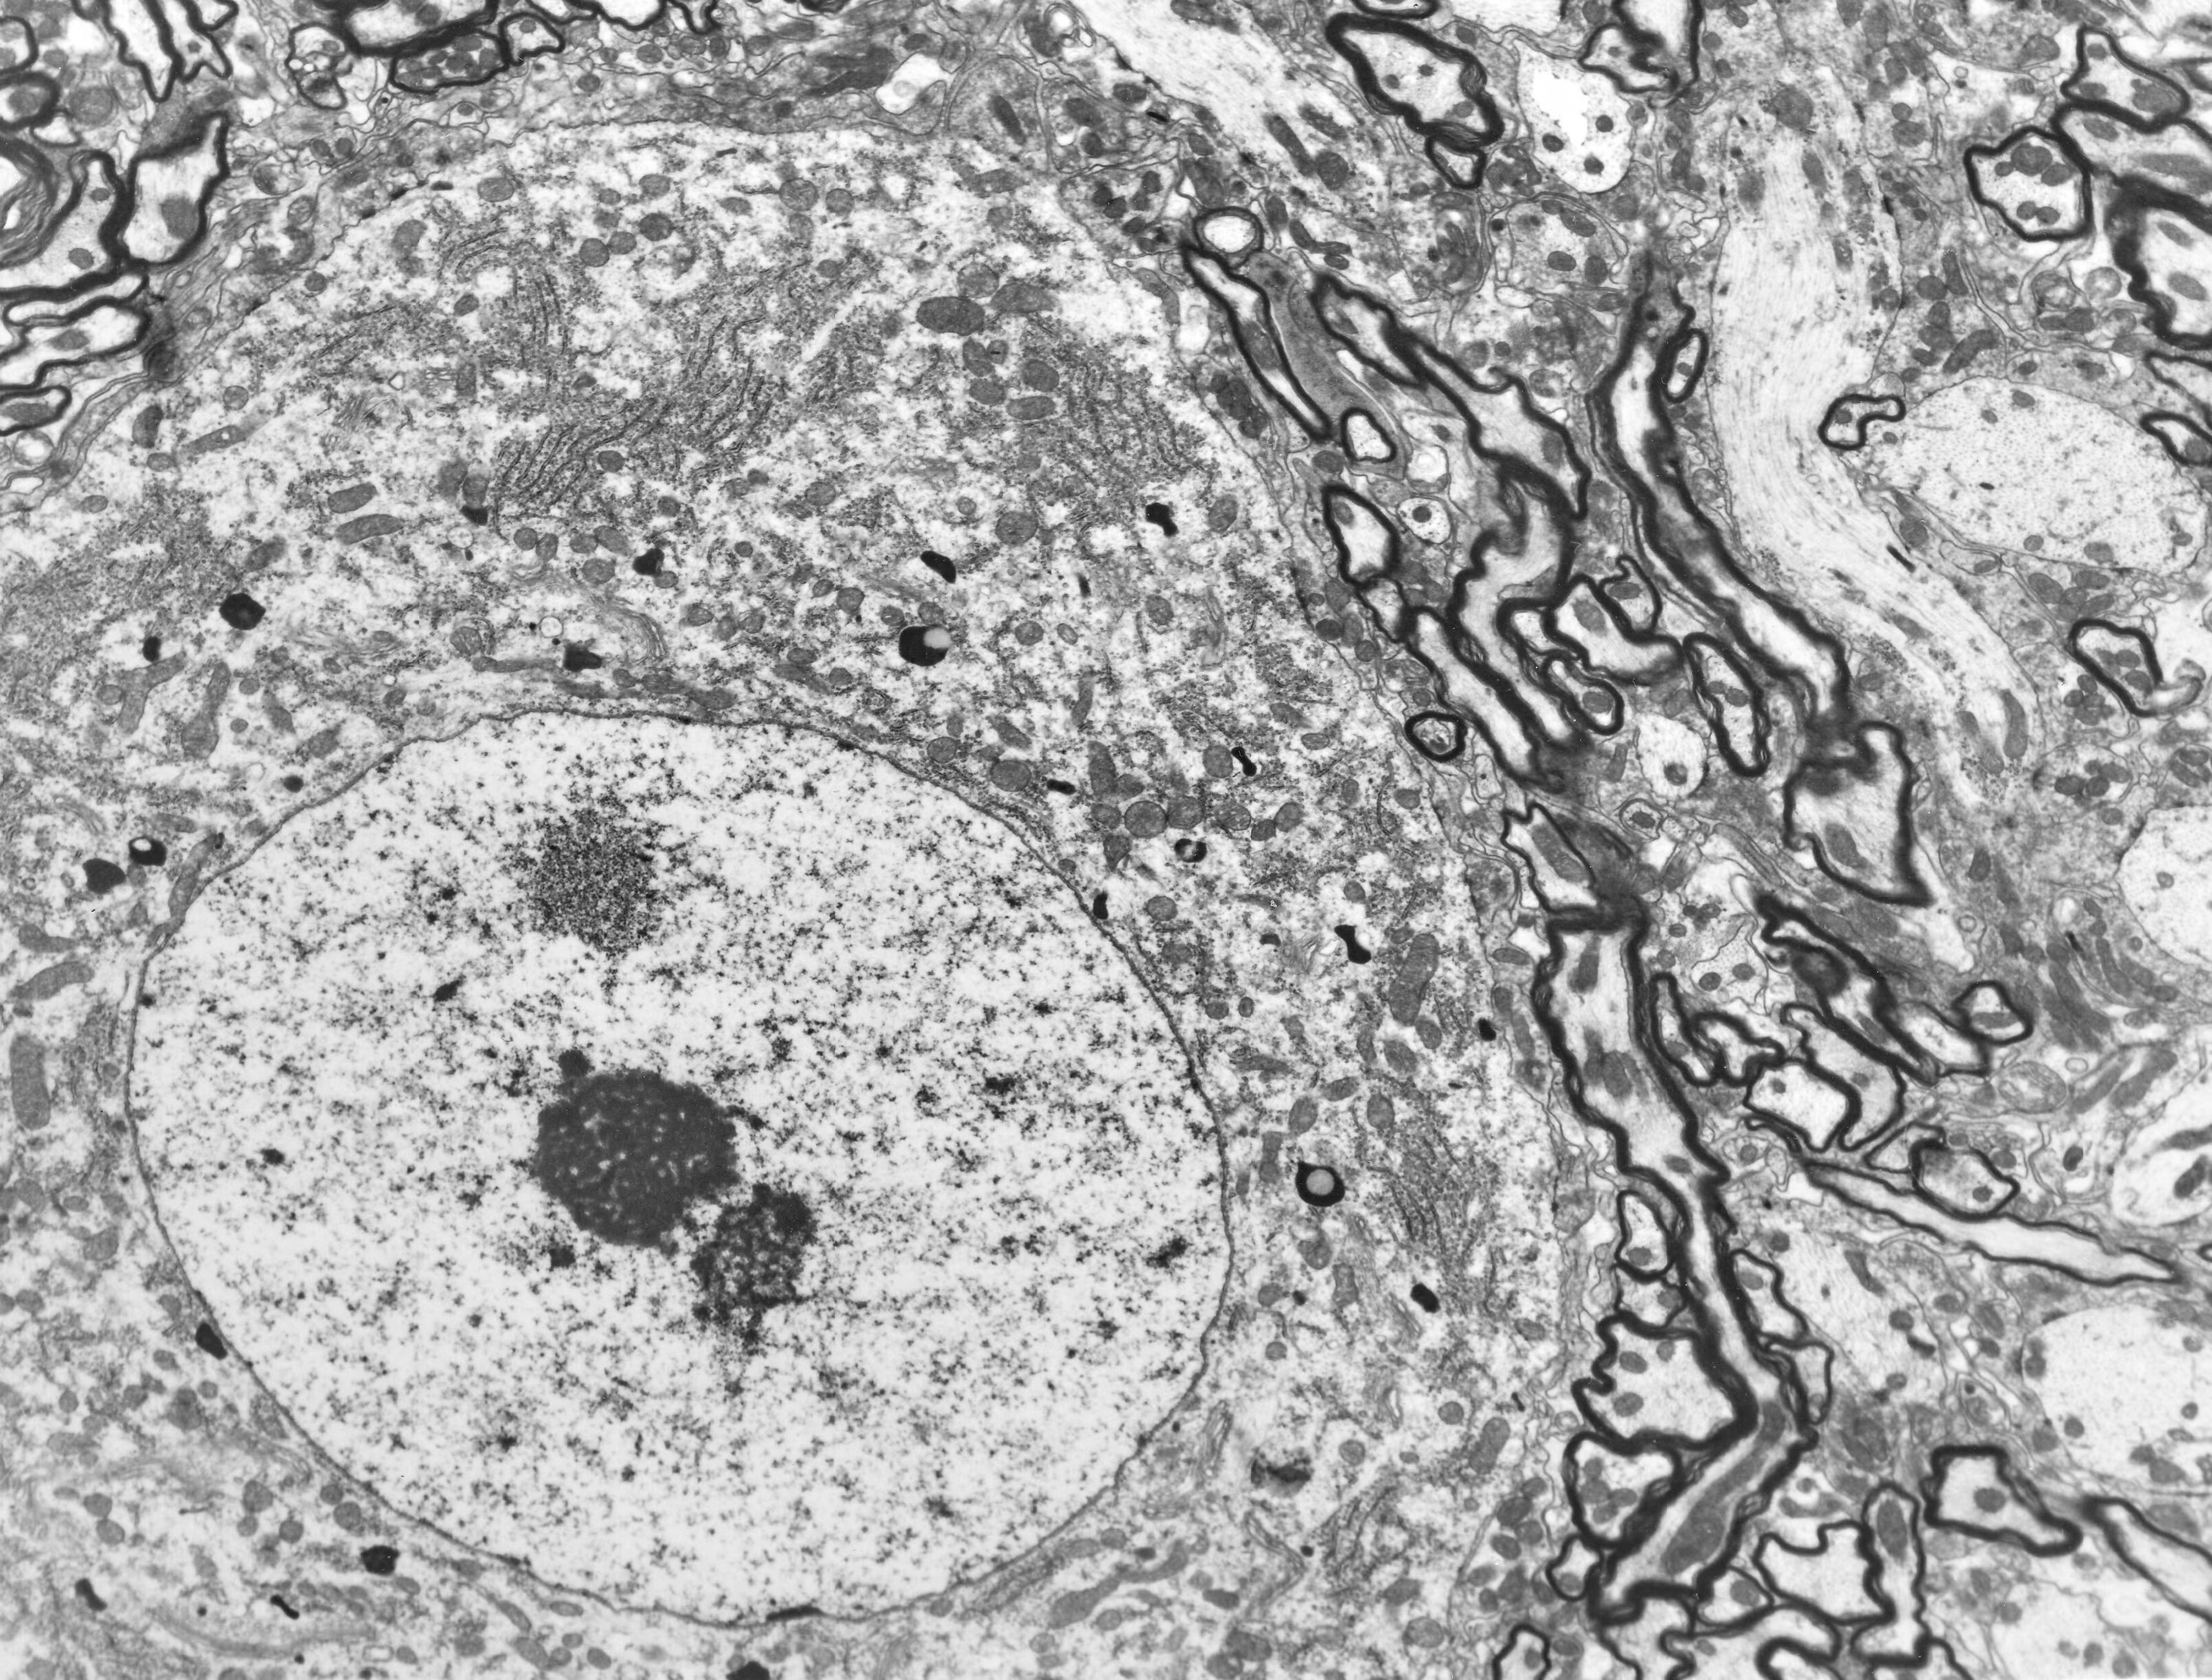

The images above are taken from the BPF’s Accreditation page. On the left, you can see the pig brain which I preserved, winning the Large Mammal prize. The cellular structure is intact and it’s easy to trace the connections between the neurons. The right-hand image shows the damage caused by traditional cryopreservation, even under ideal circumstances. Real preservation cases are far worse due to pre- and post-mortem brain damage. Maybe a superintelligence could reconstruct the structure – but it’s unclear whether the information to do so remains.

This is a section taken from a rat brain preserved 5 minutes post-mortem in a manner that’s consistent with the surgical time we can achieve with pigs. All axons, dendrites, and synapses pictured are connectomically traceable. After preservation, we stored this brain at 60°C for ~12 hours before imaging! Click through for a “Google Earth”-style presentation of the whole slice, which is around 5 GB of data.